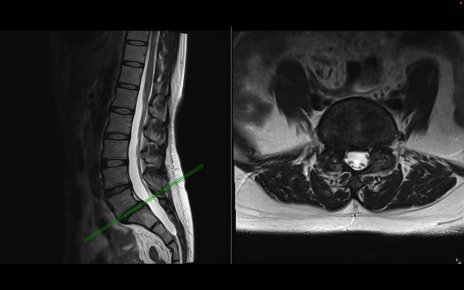

腰椎MRI

T2WI(横断像)

T2WI(矢状断像)